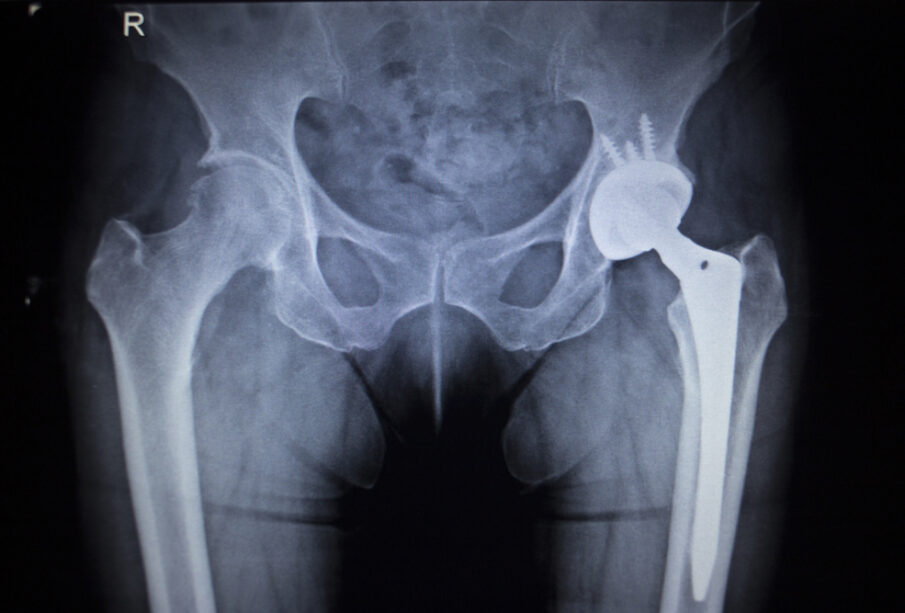

Birmingham sistema susideda iš dviejų pagrindinių dalių. Pirma, šlaunikaulio galvutė nušlifuojama, kad ant jos būtų galima uždėti metalinį dangtelį. Toliau į dubens sąnarį (acetabulumą) įtvirtinamas metalinis įdėklas. Abu elementai gaminami iš aukštos kokybės kobalto-chromo lydinio, kuris atlaiko didelę apkrovą ir sumažina skausmą, palengvindamas judėjimą.

Metalinis paviršius pagerina judesių amplitudę, sumažina diskomfortą, be to, kaulas po operacijos išlieka stipresnis. Tai leidžia ateityje atlikti pakartotines operacijas, jei jų prireiktų.

Paviršiaus keitimo metu chirurgas pašalina tik pažeistas šlaunikaulio ir sąnario ertmės dalis, o ant jų uždeda metalinius implantus. Klubo sąnario keitimo atveju pašalinama ir visa šlaunikaulio galva, ir sąnario lizdas, kurie pakeičiami naujais protezais.